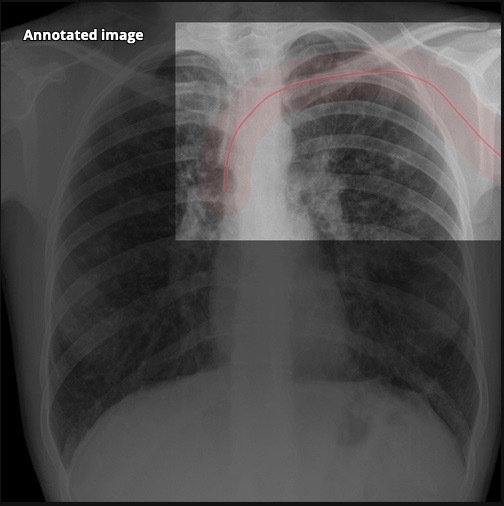

20.2 A patient has a peripherally inserted central catheter (PICC) inserted. The follow-up chest X-ray shows the tip positioned in the (Chest X-Ray shown)

a) Azygos vein

b) Coronary sinus

c) SVC

d) R atrium

e) L atrium

Correct positioning in image